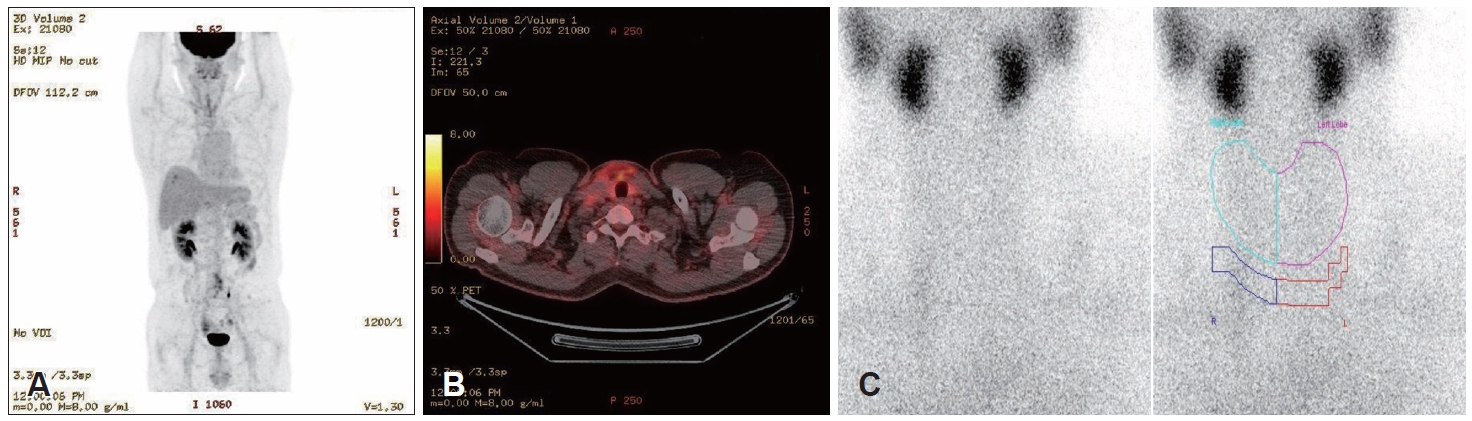

Postoperative positron emission tomography (PET)-CT, thyroid scintigraphy with technetium uptake (Fig. 4), and Tg measurement were performed to assess for residual thyroid tissue or ectopic thyroid gland. PET-CT detected no additional metastatic lesions; the technetium thyroid scan showed no visible residual thyroid tissue; and the Tg level was 0.27 ng/mL, below our laboratory’s lower limit of normal. No further treatment was indicated after multidisciplinary consultation. The patient recovered without complications and remains under routine follow-up without recurrence.

NotesAuthor Contribution Conceptualization: Yong-Dae Kim, Si-Youn Song. Data curation: Gi Moon Yoo. Formal analysis: Gi Moon Yoo, Jaebeom Park. Investigation: Yong-Dae Kim. Methodology: Gi Moon Yoo, Jaebeom Park, Si-Youn Song. Project administration: Gi Moon Yoo, Jaebeom Park. Supervision: Yong-Dae Kim, Si-Youn Song. Validation: Si-Youn Song. Visualization: Yong-Dae Kim, Si-Youn Song. Writing—original draft: Gi Moon You. Writing—review & editing: Gi Moon Yoo. Fig. 1.Preoperative ultrasonography and CT findings. A: An oval-shaped, well-defined, heterogeneously hypoechoic mass measuring 2.04×1.11 cm with low vascularity and loss of the hilum is present at right cervical level III. B-D: Axial (B and C) and coronal (D) contrastenhanced CT images show an approximately 14×15×21 mm, well-marginated, heterogeneously enhancing solid mass-like lesion at right level III (red arrows) and no definite space-occupying lesion in either thyroid lobe. Fig. 2.Histologic features of the right level III mass from fine-needle aspiration. A: Histopathology shows nuclear enlargement, multiple nuclear pseudoinclusions, and grooves, consistent with metastatic papillary thyroid carcinoma (hematoxylin-eosin, 400×). B: Immunohistochemical staining for thyroid transcription factor-1 was positive in the tumor cells (hematoxylin-eosin, 200×). Fig. 3.Histologic features of the thyroid gland. Histopathology showed 0.2×0.2 cm nodular hyperplasia at thyroid isthmus without features of papillary thyroid carcinoma (hematoxylin-eosin, 40×). Fig. 4.Postoperative positron emission tomography-CT and thyroid scan findings. A and B: Uneven 18F-fluorodeoxyglucose uptake in the anterior neck and mild uptake in both lateral necks suggest postoperative changes and reactive lymph nodes. No other hypermetabolic lesions suggest metastasis to other organs. C: Postoperative Tc-99m pertechnetate thyroid scan shows no significant radioactive accumulation. Table 1.Previous reports of ATA intermediate-risk metastatic PTC without primary tumors